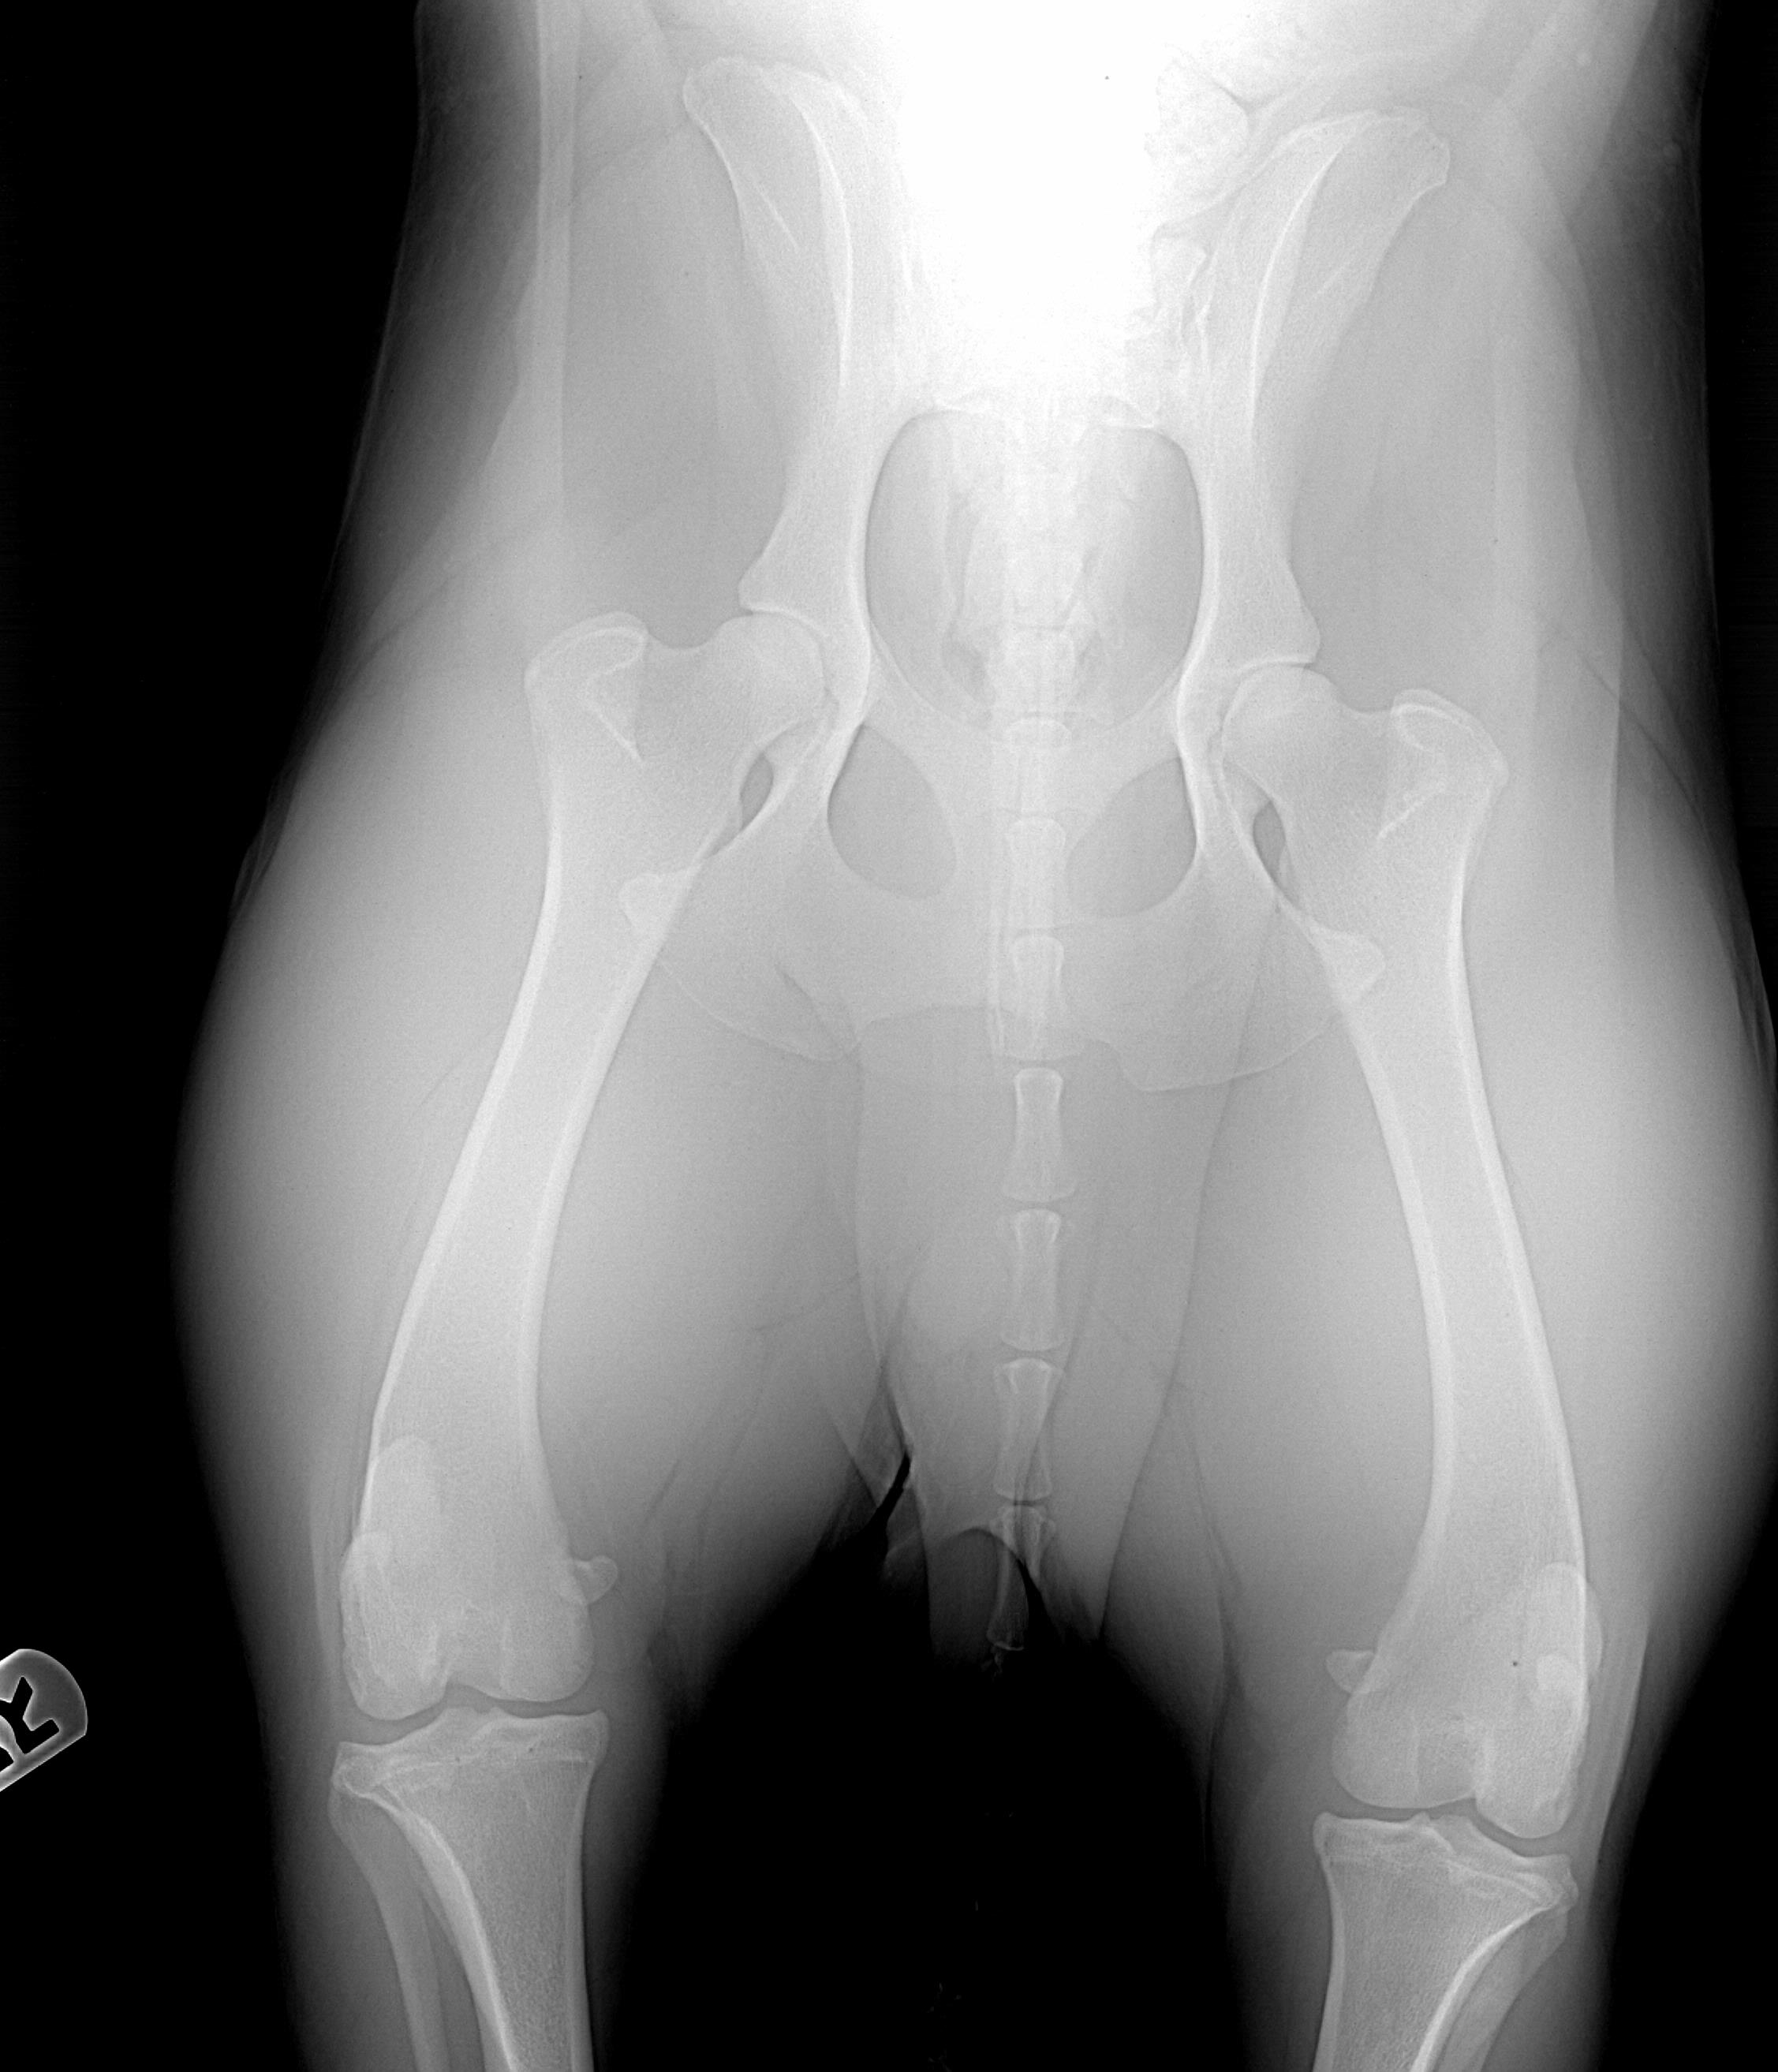

Barry's hips and elbows, taken on 1/7/08. My vet said he would be "shocked" if he did not get an Excellent but OFA gave them a Good. The third time they looked at them OFA changed one elbow from clear to Grade 1, however. We are disappointed. Both his littermates have gotten OFA Excellents, normal elbows, so that is nice. We'll try again for the perfect chocolate boy with Adam and Woody. :)